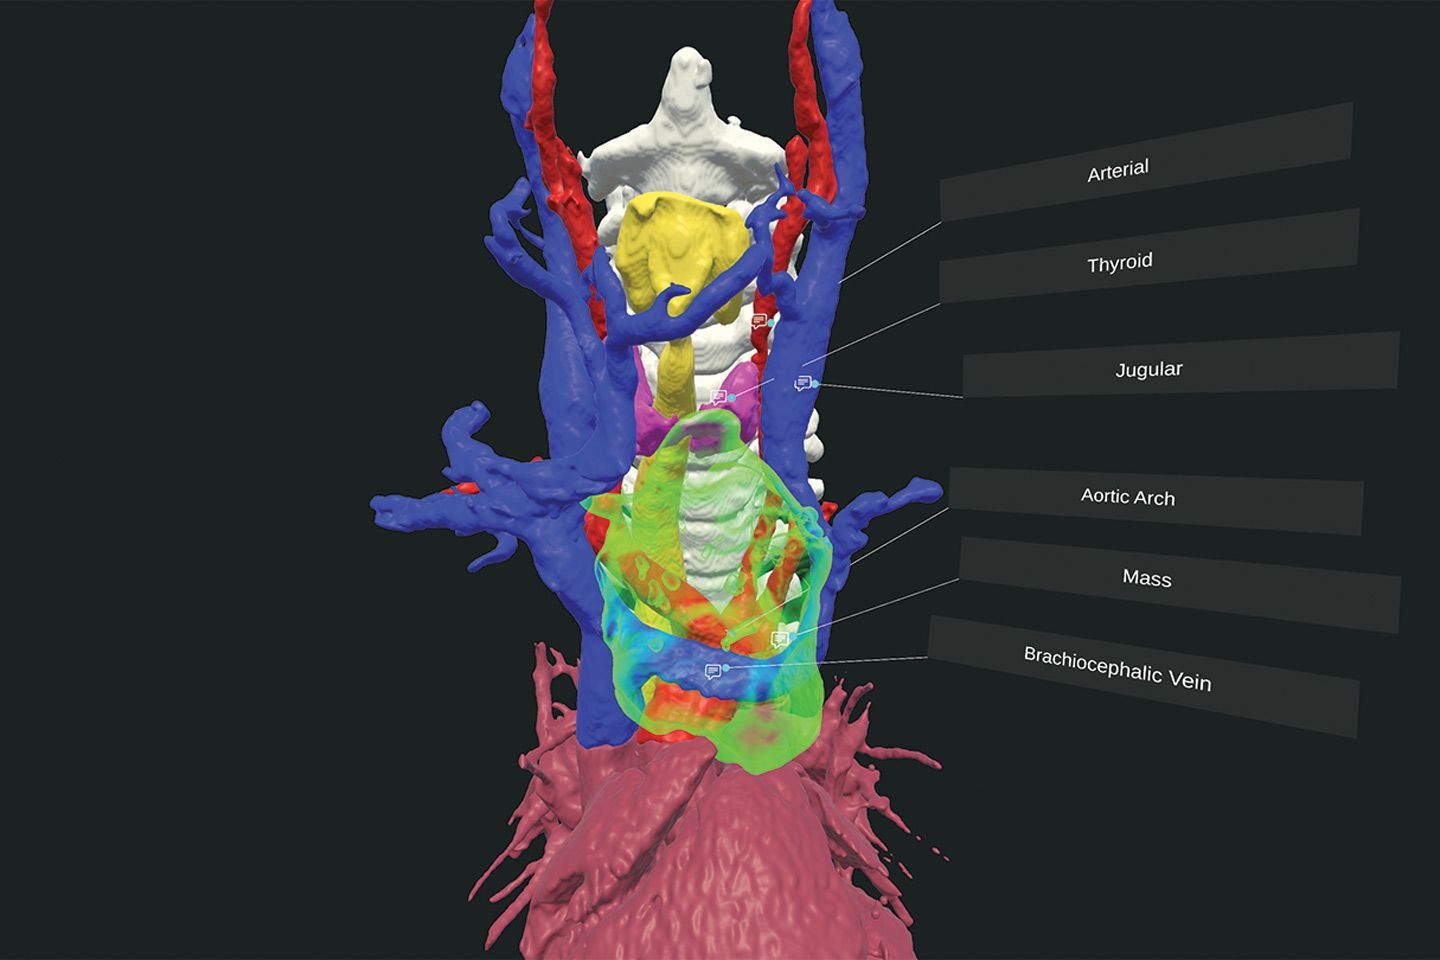

Preoperative CT scan of the patient’s chest showing the mediastinal tumor. Source: NYU Langone Health.

Virtual reality visualization of the tumor’s position near critical structures. Source: NYU Langone Health.